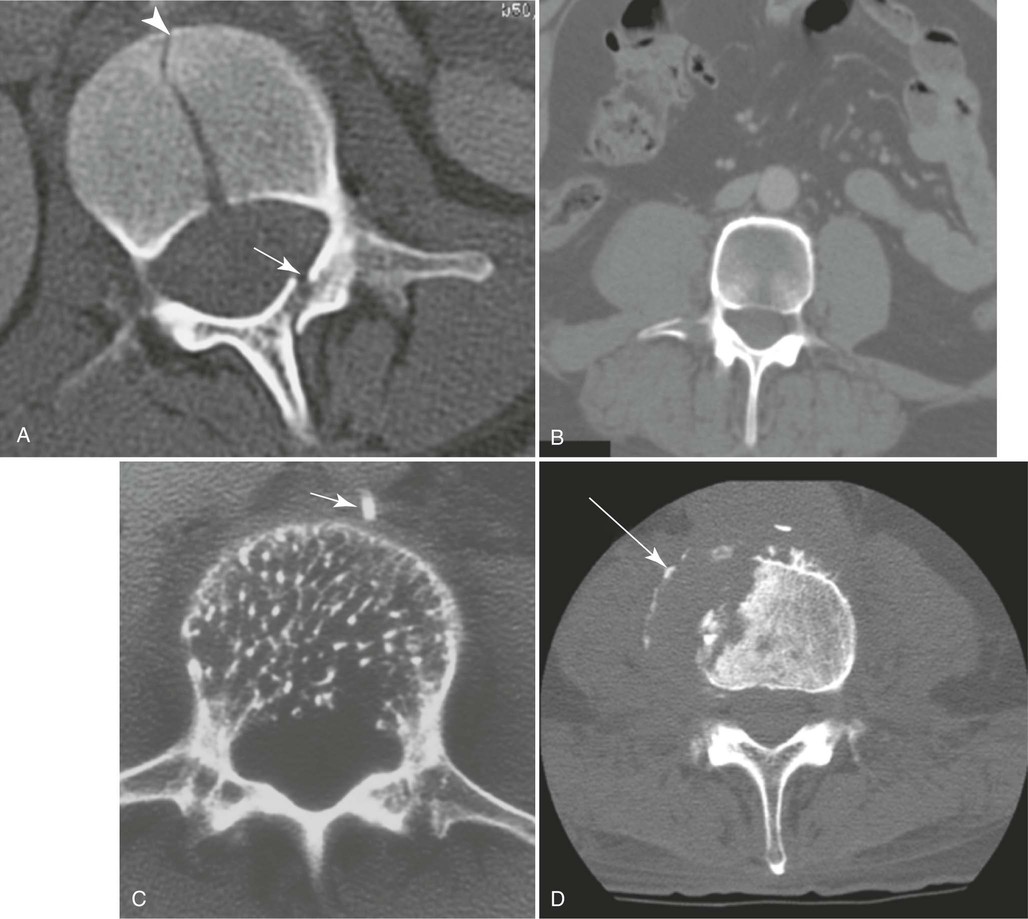

The resulting image shows an oblique projection of the lumbar or lumbosacral spine or both, showing the articular processes of the side closest to the IR. Both sides are examined for comparison (Figs. 8-97 and 8-98).

When the body is placed in a 45-degree oblique position and the lumbar spine is radiographed, the articular processes and the zygapophyseal joints are shown. When the patient has been properly positioned, images of the lumbar vertebrae have the appearance of Scottie dogs. Fig. 8-97 shows the vertebral structures that compose the Scottie dog. (See Summary of Oblique Projections, p. 382.)

The image shows an oblique projection of the lumbar or lumbosacral vertebrae, showing the articular processes of the side farther from the IR (Figs. 8-101 to 8-103). The T12-L1 articulation between the twelfth thoracic and first lumbar vertebrae, having the same direction as those in the lumbar region, is shown on the larger IR. The fifth lumbosacral joint is usually well shown in oblique positions (see Fig. 8-103).

When the body is placed in a 45-degree oblique position, and the lumbar spine is radiographed, the articular processes and zygapophyseal joints are shown. When the patient has been properly positioned, images of the lumbar vertebrae have the appearance of Scottie dogs. Fig. 8-101 identifies the vertebral structures that compose the Scottie dog. (See Summary of Oblique Projections, p. 382.)